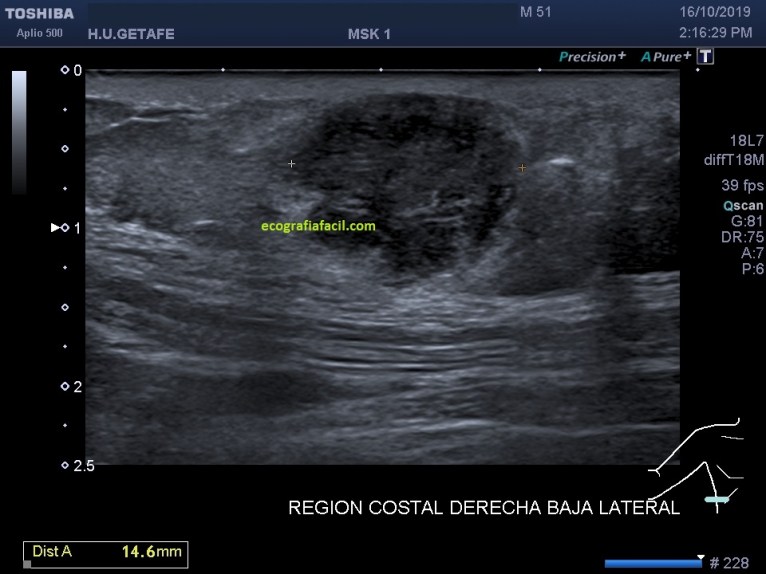

Lo primero que tenemos que tener claro es la anatomía. En la imagen «anatomía» te marco todo estratificado para que te des cuenta del nivel en el que se presenta la lesión que debemos estudiar, es importante que te fijes en la piel, si está respetada o no.

En la imagen 1 y 2, las medidas, básico en cualquier estudio de una lesión. La imagen 3 nos muestra la vascularización de la lesión, que lo está, aunque no es una vascularización exacerbada.

La LOE (lesión ocupante de espacio) es hipoecogénica, heterogénea, sólida, con bordes definidos, pero agrestes, aunque respeta tanto la piel como la fascia.